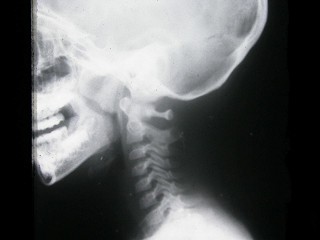

[单选题]男,5岁,反复呛咳,张口呼吸,有鼾声,鼻腔分泌物多。X线检查如图所示,最可能的诊断是()A.鼻窦炎B.鼻息肉C.扁桃体炎D.腺样体肥大E.鼻炎